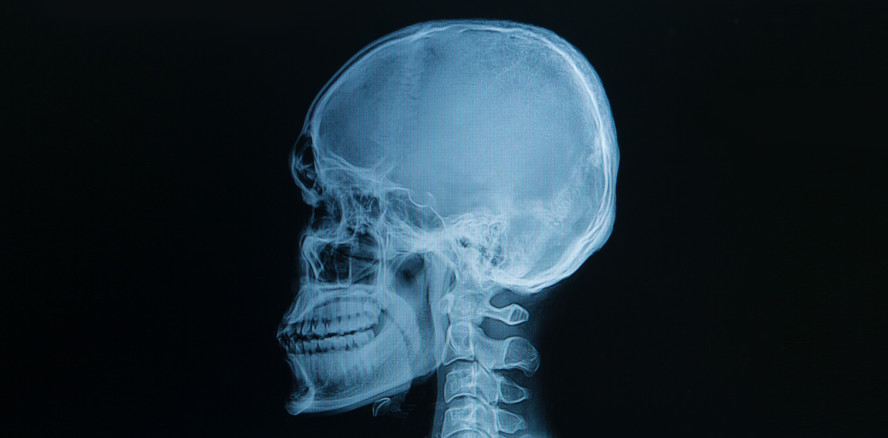

Komplettes Gesicht mit 3-D-Drucker rekonstruiert

Ärzte aus Boston geben einem kleinen Mädchen mit Lippen-Kiefer-Gaumenspalte ein neues Gesicht

Die kleine Violet (2) kam im Gegensatz zu ihrer Zwillingsschwester mit einer stark ausgeprägten Lippen-Kiefer-Gaumenspalte zur Welt. Nun wurde sie in Boston erfolgreich operiert. Für die Planung und Durchführung der Operation benutzten die Ärzte ein Modell, welches mit einem 3-D-Drucker hergestellt wurde.

Das Modell wurde aufwendig durch den 3-D-Drucker Schicht für Schicht aus Harz und Acryl gefertigt. Gut zu erkennen war so für das Ärzteteam um Dr. John Meara, wie die Knochenstruktur unter Haut und Muskeln aufgebaut war und wo genau geschnitten werden musste. Anhand dieses Modells wurde auch eine Schablone erstellt, die während der Operation für das korrekte Ansetzen der Schnitte in den Knochen benutzt wurde. Nicht viele Ärzte haben Erfahrung in der Durchführung dieser komplizierten Operation. Dr. Meara hatte vor Violet bereits vier andere Patienten mit ähnlichen Spalten erfolgreich operiert. Auch dieses Mal war er erfolgreich und es gelang, Violets Augen wieder näher zur Mitte zu bringen und die Gesichtsknochen in eine annähernd normale Position zu bringen.